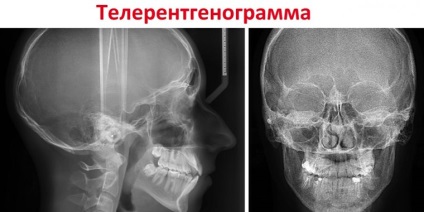

A rendszer segítségével a munkacsoport tehető világossá panoráma képet a koponya profilja és teljes arcát. 3 elválasztott alkotnak diagnózist.

Specialista, attól függően, hogy annak eldöntése céljából egy vagy több képet, ki kell töltenie a diagnózis:

- Front. Ez a fajta vizsgálat diagnosztikai célokra megkezdése előtt protetikai kezelés alapvető fontosságú. A kép készült a fej hátsó és az első. Azt teszi, hogy egészen világos, hogy a meglévő gyulladás, arc aszimmetriája és törések.

- Munkacsoport oldalnézetben szükséges betegek malocclusion. Oldalsó lövés, akkor a legpontosabban azonosítani patológia felépítése a fogászati rendszert, és hozzon létre egy optimális tervet Javítás. A kutatás ezen vetülete, hogy meghatározza a szög az alsó elülső fogak, különösen azok helyét, valamint figyelemmel kíséri a kezelést, és kiszámítja annak időtartamát. Mindenki, aki azt tervezi, hogy javítsa a nadrágtartó, mindig biztos lehet abban, hogy ezt a képet.

- A tengelyirányú (vagy az állán) teleroentgenography hozzárendelt csak kiegészítésképpen diagnosztikai együtt más típusú TRH. Ez a tanulmány a legteljesebb képet az alakja és szerkezete a fej három dimenzióban. Meg kell határozni a változások a szerkezetben az orrüreg és a sinus maxillaris arccsontja. Általánosan használható, ha a szükséges beágyazódás felső elülső fogak.